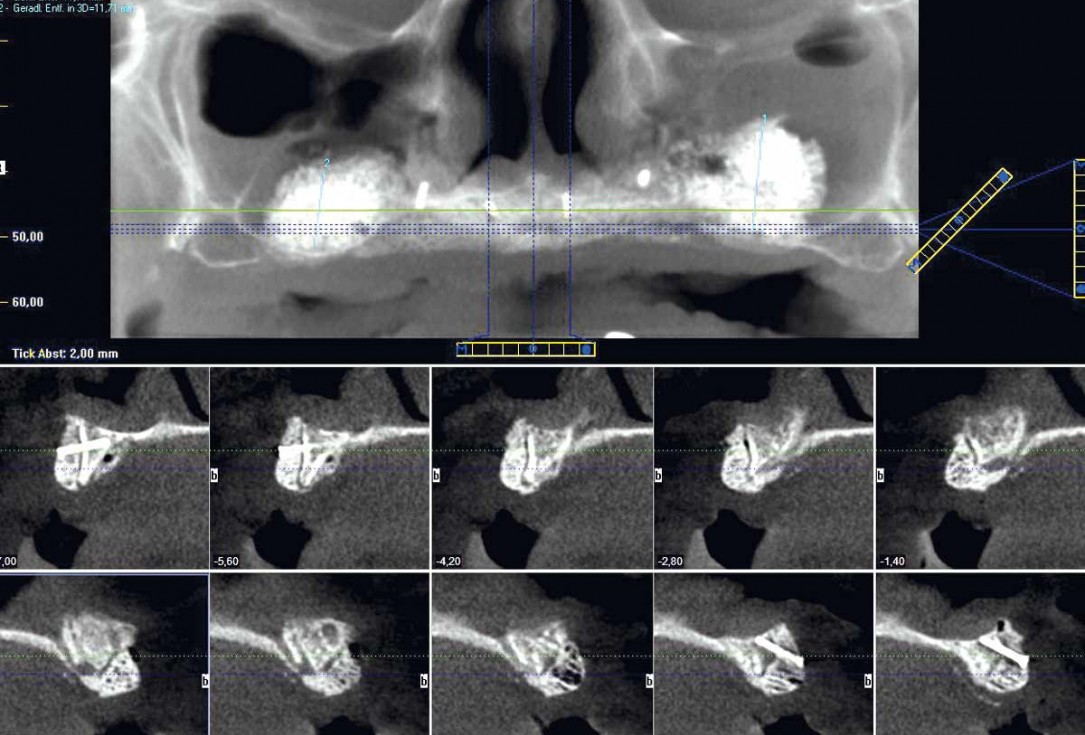

3/23 - Preoperative radiological situation – severely atrophic maxilla

Full arch reconstruction of the maxilla with maxgraft® bonebuilder - Dr. M. Erbshäuser